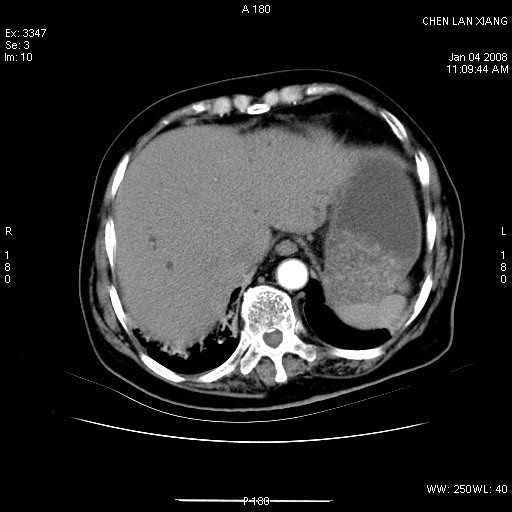

标题: CT11180:女,76岁,腹痛3-4天 [打印本页]

女,76岁,腹痛3-4天,b超示:肝内实性肿物,胆囊强回声,胆总管扩张.

考虑:1、胆总管下端结石伴梗阻性肝内外胆管扩张(肝左叶外侧段肝内胆管多发结石、胆管炎);

2、肿囊癌累及肝,不除外 黄色肉芽肿性胆囊炎。

1 胆总管末端结石伴肝内胆管结石,肝内外胆管扩张。2 胆囊扩大,胆囊壁不规则增厚,内见软组织密度影。考虑:慢性胆囊炎,不除外胆囊癌!

标题: 肝右叶病灶

胆囊癌侵犯肝右叶?

1)胆囊癌伴肝脏转移。2)胆总管下端结石、肝内胆管结石伴肝内外胆管扩张。